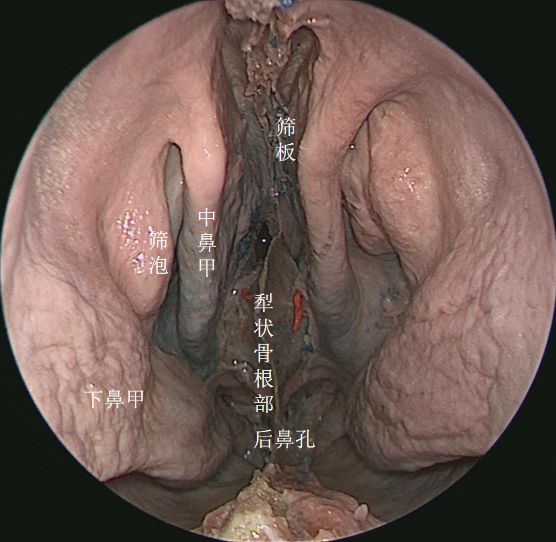

↑ 去除鼻中隔,向上方观察筛板

去除左侧筛窦,向上方观察筛顶 ↓

↑ 去除鼻中隔观察鼻腔后壁结构